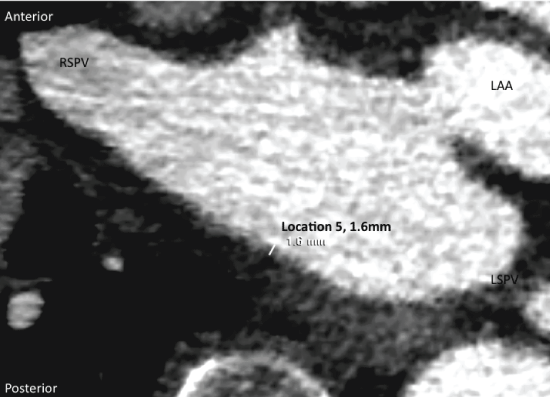

It was measured from axial views in 12 preselected locations (Figure 1) based on the differences in Hounsfield Units (HU) for various compartments (contrasted blood 200-600 HU, left atrial wall tissue 50 HU and pericardial fat - 100) and with anatomical fix points (the pulmonary veins and the left atrial appendage) as guidance in location determination (Figure 2). We included 3 locations at the roof (right, middle, left), 3 locations at the floor (right, middle, left), 4 locations at posterior wall (right, middle, middle-superior, left), 1 at the Left Lateral Ridge (LLR), and 1 at the mitral isthmus as previously described [11]. The LAWT was assessed as the mean of 3 manually performed measurements in each preselected location, or excluded if not possible due to anatomical anomalies or motional artefacts - 23 measurements (2.0%) in the AF group and 52 measurements (4.7%) in controls out of a total of 1128 measurements. Global LAWT was calculated as the mean thickness in each patient based on a summed mean of all preselected locations. In addition regional differences in LAWT and relative thicknesses (location thickness/mean thickness) were evaluated and compared between the two groups.

Figure 1: Preselected locations for left atrial wall thickness assessment, modified from Beinart, et al. [11]. LIPV: Left Inferior Pulmonary Vein; LSPV: Left Superior Pulmonary Vein; RIPV: Right Inferior Pulmonary Vein; RSPV: Right Superior Pulmonary Vein. View Figure 1

Figure 2: Method demonstration of left atrial wall thickness assessment, in this case location 5. Axial view. RSPV: Right Superior Pulmonary Vein; LAA: Left Atrial Appendage. View Figure 2